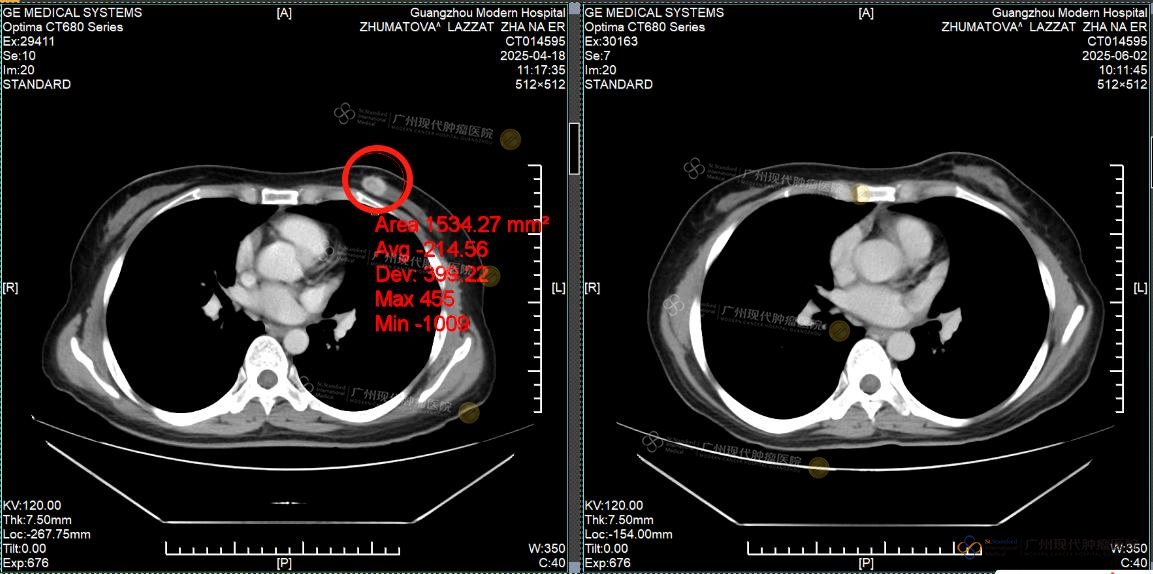

Tumor payudara: sebelum pengobatan VS sesudah pengobatan

Pada April 2025, Lazzat datang ke rumah sakit kami ditemani oleh kakaknya dan menjalani pemeriksaan menyeluruh. Hasil CT menunjukkan bahwa terdapat massa tumor pada payudara kiri dengan ukuran sekitar 2×1cm, serta banyak lesi metastasis di hati, dengan diameter nodul terbesar lebih dari 4cm. Fungsi hati juga telah terpengaruh oleh tumor.

Setelah menjalani 2 siklus pengobatan, tumor payudara Lazzat berhasil dihilangkan sepenuhnya dan tidak terdeteksi lagi saat pemeriksaan ulang. Lesi metastasis di hati menyusut lebih dari setengah, fungsi hati kembali normal, dan penanda tumor seperti CEA dan CA153 menunjukkan penurunan yang signifikan. Berkat perawatan yang cermat dari tenaga medis, fungsi hatinya membaik, rasa lelah dan lemas pun berkurang secara nyata, dan ia kembali merasakan semangat hidup yang sudah lama hilang.